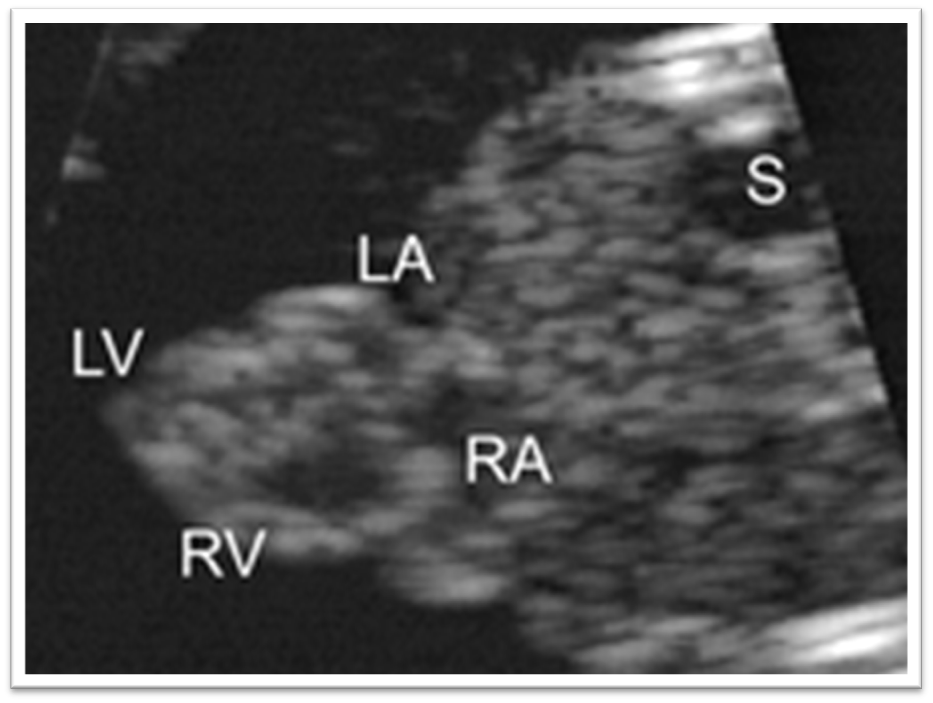

Label this image.

What view is a single ventricle best evaluated in?

4-chamber